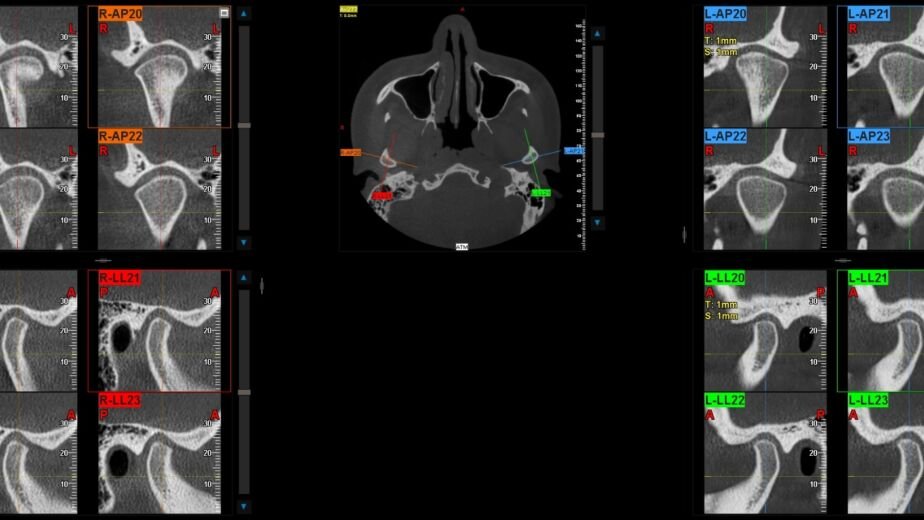

El estudio TAC macizofacial ofrece múltiples beneficios para la salud bucal, comenzando por su capacidad para detectar problemas en etapas tempranas. Gracias a su alta resolución y precisión, los dentistas pueden identificar caries ocultas, fracturas óseas o infecciones que no serían visibles en radiografías convencionales. Esto permite un diagnóstico más certero y un tratamiento más efectivo, lo que puede prevenir complicaciones futuras.

Otro beneficio significativo es su utilidad en la planificación de tratamientos complejos. Por ejemplo, en el caso de implantes dentales, el TAC proporciona información detallada sobre la densidad ósea y la ubicación de estructuras vitales como nervios y senos paranasales. Esta información es crucial para asegurar que el implante se coloque correctamente y minimizar riesgos durante el procedimiento.

El estudio TAC macizofacial se recomienda en diversas situaciones clínicas. Por ejemplo, es particularmente útil en casos donde hay sospecha de patologías como quistes o tumores en la región maxilofacial. También se utiliza en pacientes que requieren cirugía ortognática o implantes dentales, ya que proporciona información esencial sobre la anatomía del paciente.

Los resultados obtenidos a partir de un estudio TAC macizofacial son fundamentales para guiar el tratamiento dental adecuado. Las imágenes generadas permiten identificar anomalías estructurales como quistes, tumores o fracturas óseas con gran precisión. Además, se pueden evaluar condiciones como sinusitis maxilar o problemas relacionados con las articulaciones temporomandibulares (ATM), lo que ayuda a formular un diagnóstico integral.

Una vez analizados los resultados, el dentista puede discutir con el paciente las opciones de tratamiento más adecuadas basadas en los hallazgos del TAEsto no solo mejora la calidad del tratamiento recibido, sino que también proporciona al paciente una comprensión clara de su situación dental y las medidas necesarias para mejorar su salud bucal.

A partir de un estudio tac macizofacial se pueden obtener imágenes tridimensionales de la estructura ósea y dental, que permiten un diagnóstico preciso y la planificación de tratamientos dentales.